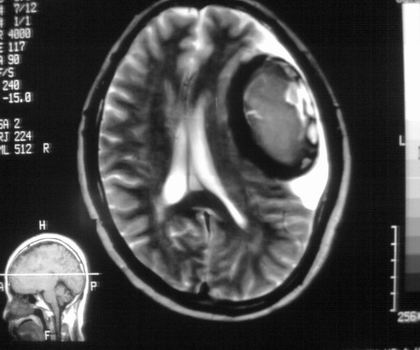

以下是引用影像孺子牛在2008-4-29 21:20:00的发言:[br]首先病变定位在脑外,根据ct密度及mri信号特征考虑慢性硬膜下血肿不连续环形钙化。

以下是引用周战梅在2008-4-29 23:12:00的发言:[br]脑外病变,蛛网膜下腔增宽,囊壁点状、环形钙化,增强扫描呈不均匀环状强化,考虑为囊性脑膜瘤可能性大,慢性脓肿、血肿机化、胆脂瘤不能除外。